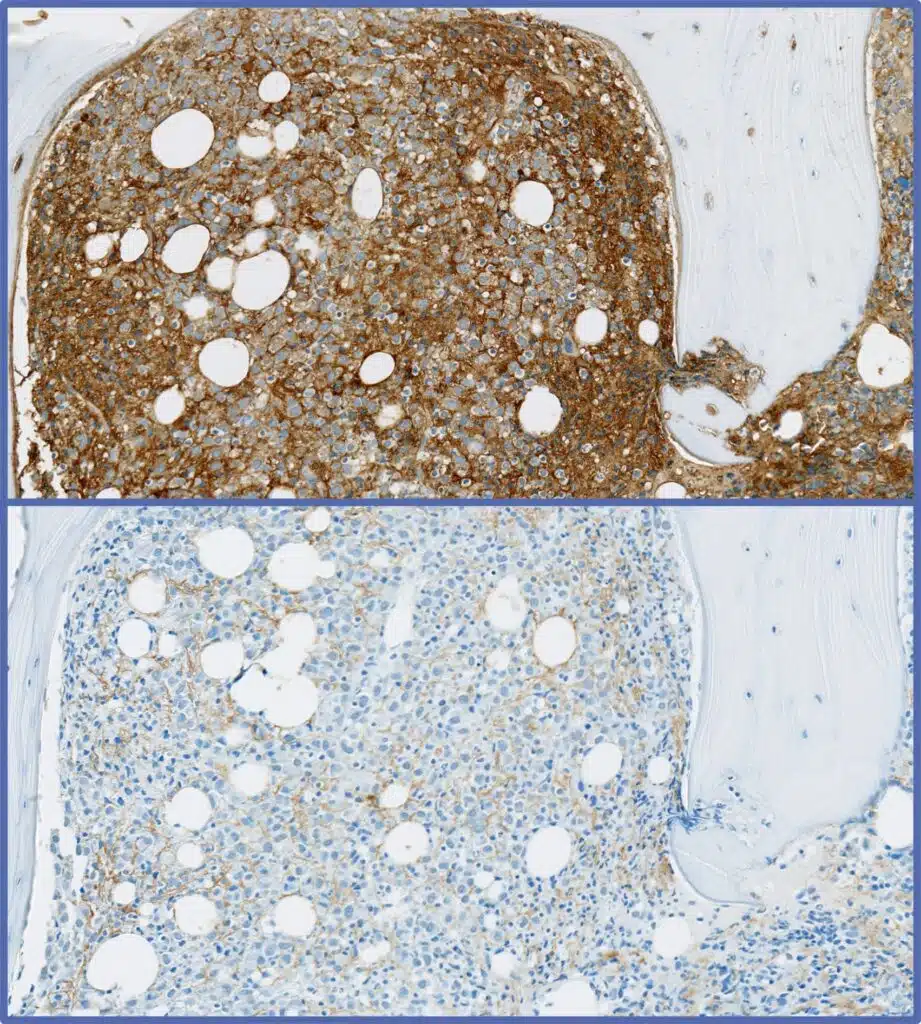

Kappa/Lambda Positivity In Plasma Cell Myeloma

Histopathology analysis with markers such as CD138, kappa, lambda run in CLIA accredited laboratories

Multiplex / simplex IHC

250+ biomarkers / protocols

Board certified pathologists